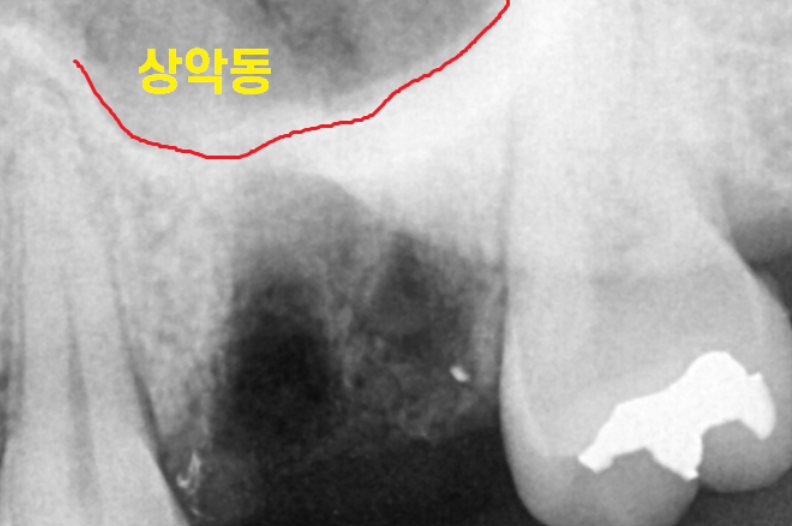

수술 전 치아에 염증이 있었습니다.

염증이 있는 상태에서는

윗니 어금니 발치 중 상악동이 뚫릴 수도 있는데요.

발치 후 사진입니다.

미리 구조물을 x-ray로 확인을 하고 뽑아서 문제없이

안전하게 뽑을 수 있었습니다.